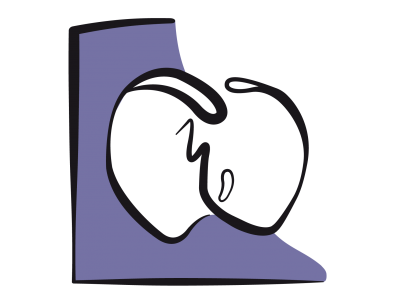

Mais si la cavité du VG se rétrécit au point que la paroi postéro-basale se déplace vers l’avant, le point de coaptation de la mitrale avance en direction de la chambre de chasse du VG (CCVG); l’occlusion n’a plus lieu sur le bord distal des feuillets mais entre l'extrémité du feuillet postérieur et le corps du feuillet antérieur. La partie distale de ce dernier flotte alors dans la cavité du VG, et l'élévation de la pression intraventriculaire la repousse antérieurement en direction de la CCVG. Par effet Venturi, elle est ensuite aspirée dans la CCVG, qu'elle occlut plus ou moins complètement. C’est le SAM (systolic anterior motion), qui survient en méso-systole (Figure 27.5) [4,17].

Figure 27.5 : Obstruction dynamique de la CCVG. A : situation normale. Le point de coaptation des feuillets mitraux est situé au tiers postérieur du diamètre antéro-postérieur (flèches bleues); en systole, la course radiaire de la paroi postéro-basale (*) est plus faible que celle de la paroi antéro-latérale; elle est activée électriquement en dernier. B: si le VG devient très petit par hypovolémie, la paroi postérieure avance en direction de la CCVG (flèche violette), parce que la zone antérieure est la jonction mitro-aortique qui est un point fixe (trigone fibreux); le point de coaptation est alors projeté vers la CCVG. En protosystole, la coaptation a lieu entre l'extrémité du feuillet postérieur et le corps du feuillet antérieur, dont la partie distale se retrouve flottant dans le VG et non en application contre le feuillet postérieur. C : en mésosystole, la pression intraventriculaire pousse le feuillet antérieur en direction de la CCVG (flèche violette) où l'éjection a commencé; celui-ci est alors aspiré par effet Venturi (flèche bleu pâle) et vient bloquer la CCVG (SAM: systolic anterior motion). Le débit aortique baisse soudainement, et la réouverture de la valve mitrale provoque une insuffisance méso-télésystolique (IM). MPP: muscle papillaire postérieur.

L’imagerie bidimensionnelle est le seul moyen de mettre en évidence un phénomène qui peut accompagner l’hypovolémie : l’obstruction dynamique de la chambre de chasse du VG ou effet CMO, par analogie avec la cardiomyopathie obstructive. Normalement, le point de coaptation de la valve mitrale est maintenu éloigné de la chambre de chasse par trois mécanismes: 1) il est situé au tiers postérieur du diamètre de la valve; 2) la paroi postérieure a moins de course radiaire que les parois antérieure et latérale; 3) la partie postéro-basale est activée électriquement en dernier (Vidéo). Lorsqu’elle s’élève en systole, la pression intraventriculaire maintient l’occlusion de la mitrale en appuyant les deux feuillets l’un contre l’autre par leurs bords distaux.

Mais si la cavité du VG se rétrécit au point que la paroi postéro-basale se déplace vers l’avant, le point de coaptation de la mitrale avance en direction de la chambre de chasse du VG (CCVG); l’occlusion n’a plus lieu sur le bord distal des feuillets mais entre l'extrémité du feuillet postérieur et le corps du feuillet antérieur. La partie distale de ce dernier flotte alors dans la cavité du VG, et l'élévation de la pression intraventriculaire la repousse antérieurement en direction de la CCVG. Par effet Venturi, elle est ensuite aspirée dans la CCVG, qu'elle occlut plus ou moins complètement. C’est le SAM (systolic anterior motion), qui survient en méso-systole (Figure 27.5) [4,17].

Figure 27.5 : Obstruction dynamique de la CCVG. A : situation normale. Le point de coaptation des feuillets mitraux est situé au tiers postérieur du diamètre antéro-postérieur (flèches bleues); en systole, la course radiaire de la paroi postéro-basale (*) est plus faible que celle de la paroi antéro-latérale; elle est activée électriquement en dernier. B: si le VG devient très petit par hypovolémie, la paroi postérieure avance en direction de la CCVG (flèche violette), parce que la zone antérieure est la jonction mitro-aortique qui est un point fixe (trigone fibreux); le point de coaptation est alors projeté vers la CCVG. En protosystole, la coaptation a lieu entre l'extrémité du feuillet postérieur et le corps du feuillet antérieur, dont la partie distale se retrouve flottant dans le VG et non en application contre le feuillet postérieur. C : en mésosystole, la pression intraventriculaire pousse le feuillet antérieur en direction de la CCVG (flèche violette) où l'éjection a commencé; celui-ci est alors aspiré par effet Venturi (flèche bleu pâle) et vient bloquer la CCVG (SAM: systolic anterior motion). Le débit aortique baisse soudainement, et la réouverture de la valve mitrale provoque une insuffisance méso-télésystolique (IM). MPP: muscle papillaire postérieur.